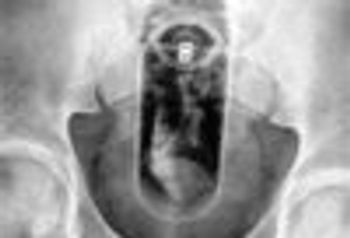

This is a case of non-abuse: the foreign body was an attempt at self-stimulation.